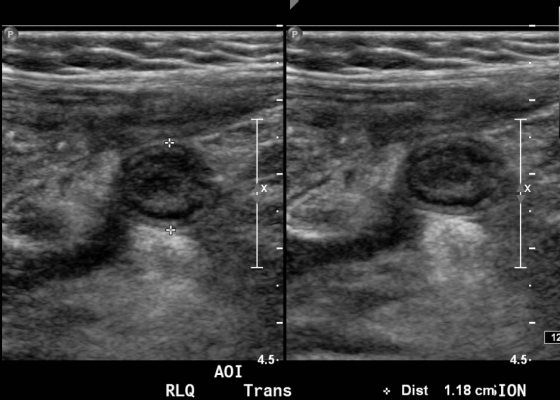

A Toddler with Abdominal Pain and Emesis

DOI: https://doi.org/10.21980/J8XW2PIn the long axis video, the appendix appears as an enlarged, non-compressible, blind-ending tubular structure (white arrow) with distinct appendiceal wall layers and lack of peristalsis. In the short axis video, the appendix appears as a target sign (yellow arrow) between the abdominal and psoas muscles. The maximal outer diameter (MOD) measures 11.8mm and the appendix wall measures 0.17mm. There is trace adjacent free fluid and echogenic periappendiceal fat. Transverse axis video and image (red arrow) demonstrate that the appendix is not compressible. These findings are consistent with acute appendicitis.